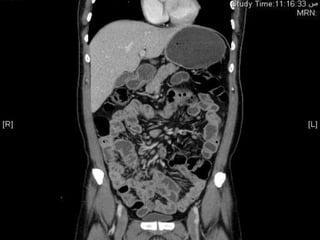

Pt underwent CT scan of the abdomen

• Work up :

jejunization of the ileum

 CT abdomen and pelvis with IV contrast

FINDINGS :

Multiple mesenteric lymphadenopathies

, largest one measuring 1.7cm.

Mild hepatomegaly.